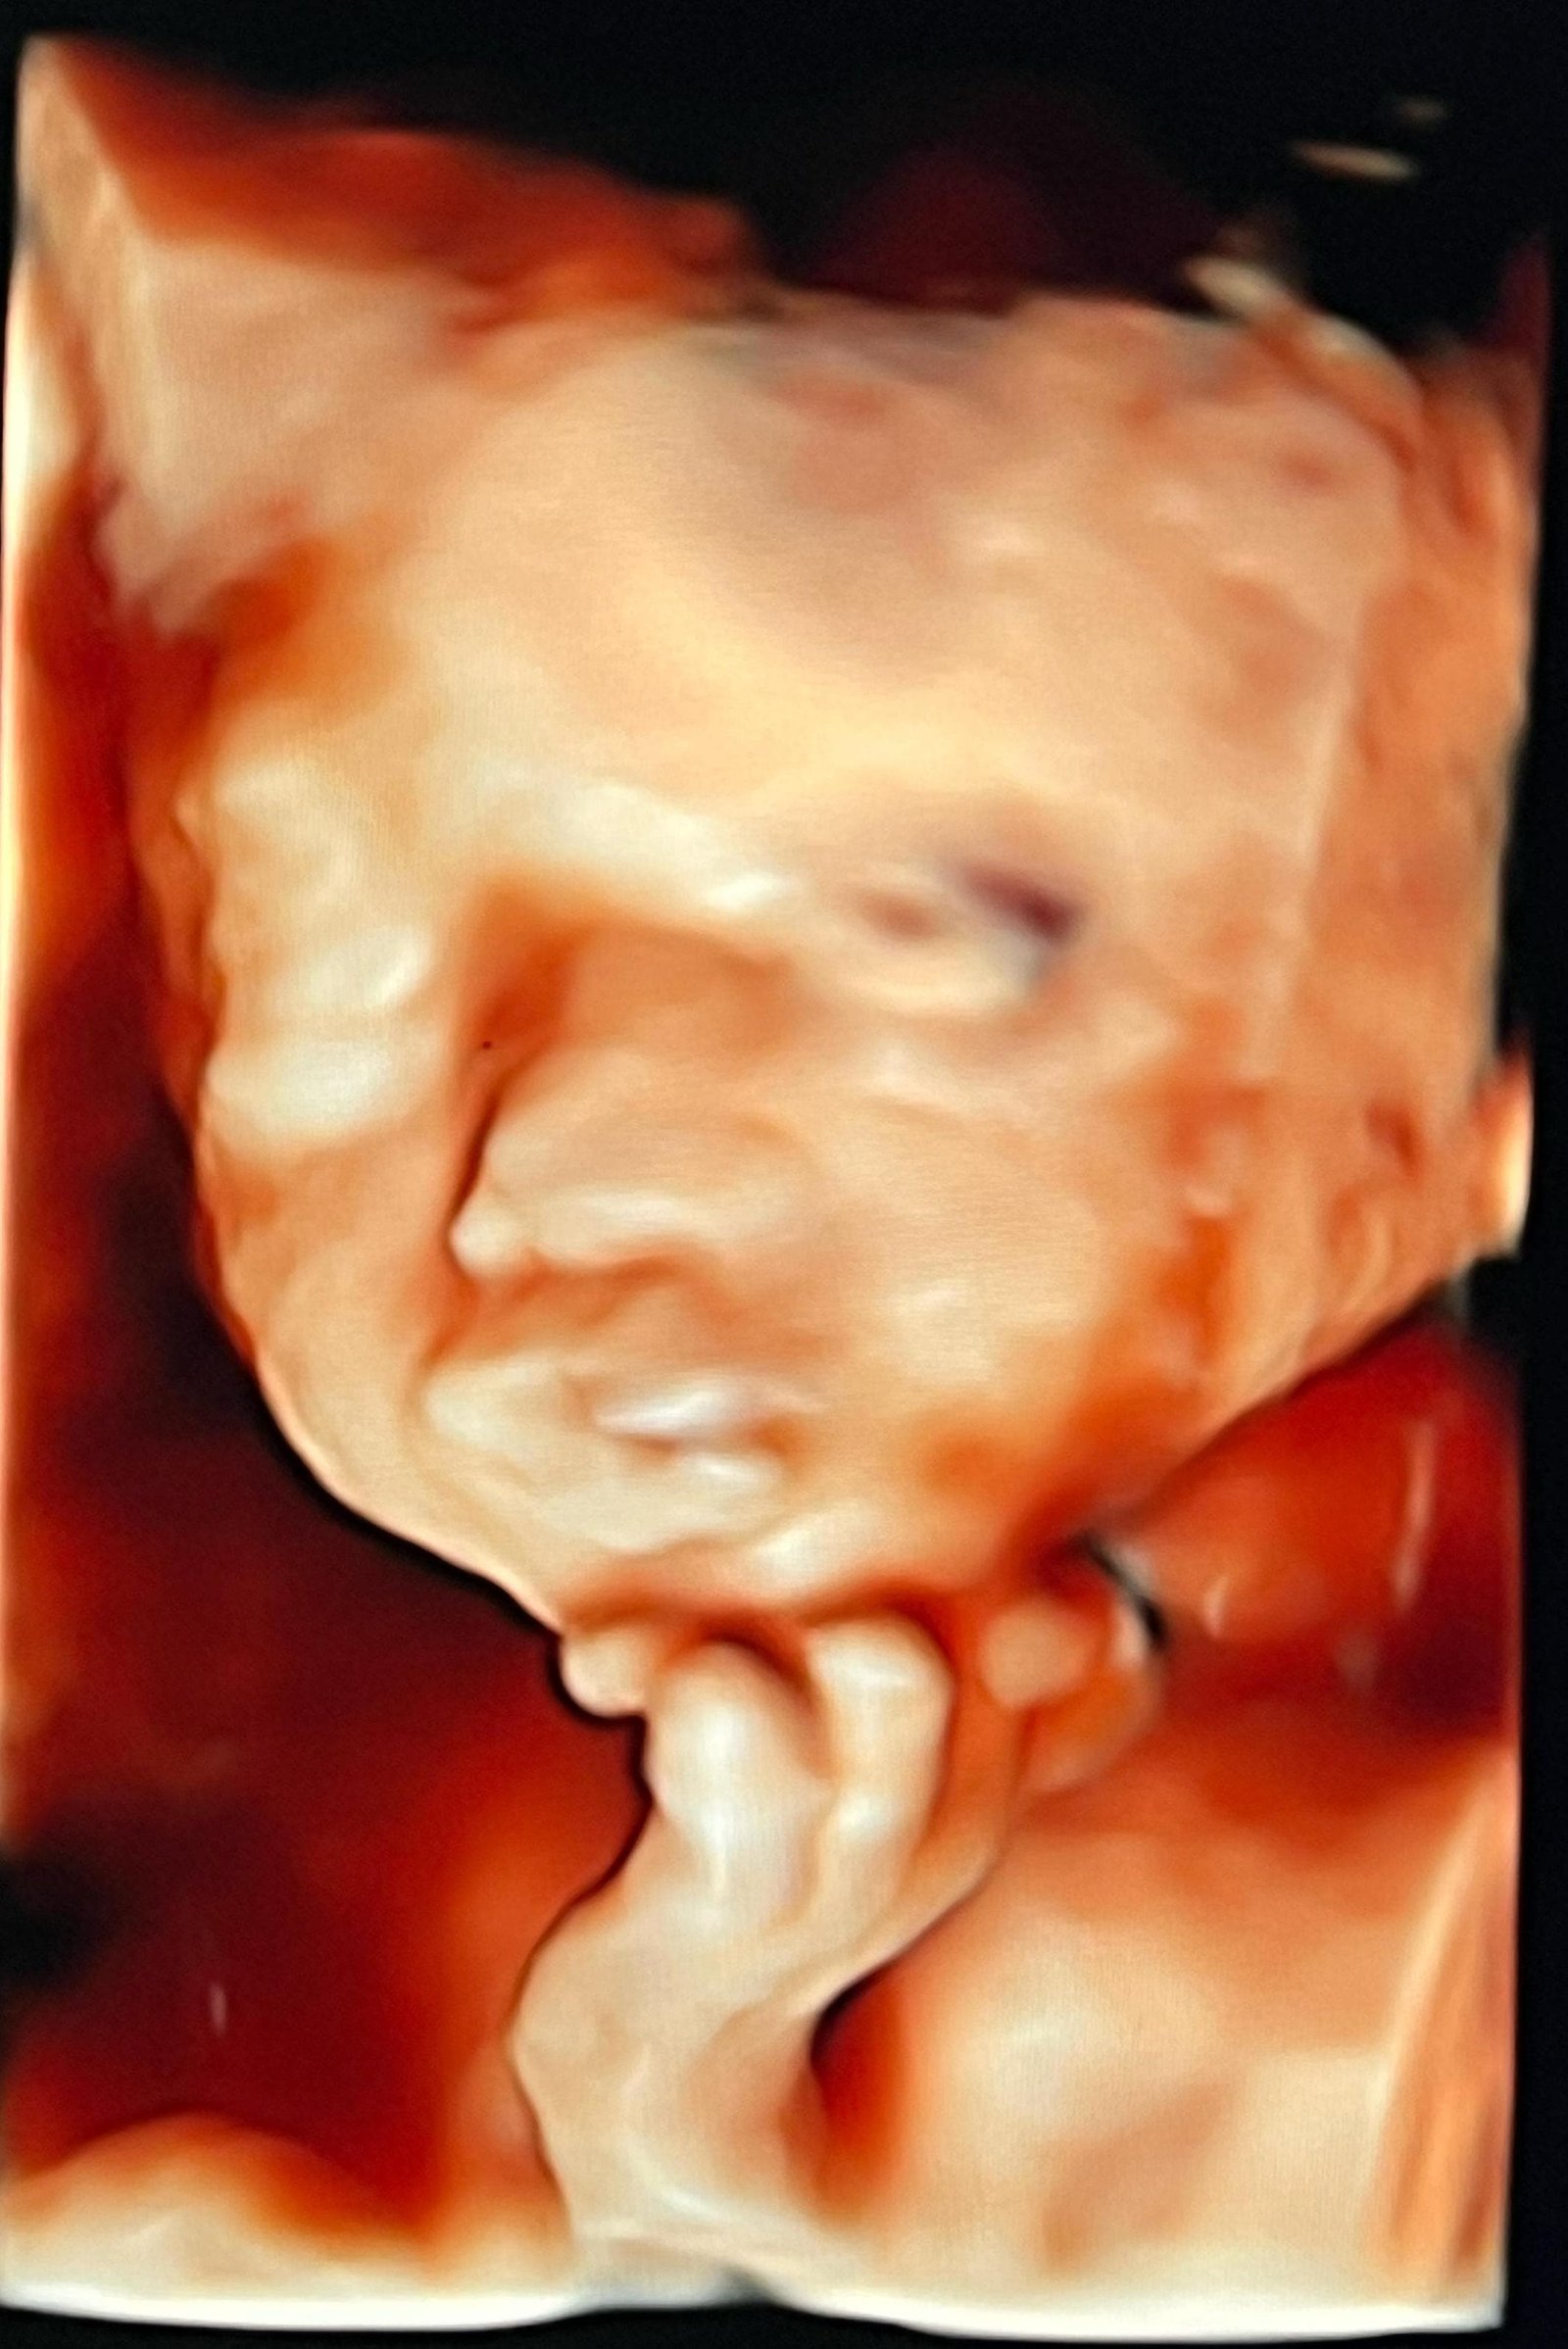

USG 4D Terbaik di Sidoarjo Hanya di www.usghalobunda.com

Tips Memaksimalkan Pemeriksaan USG 4D